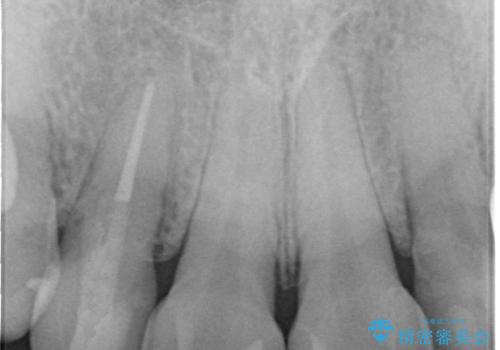

下の前歯との距離(クリアランス)が大きくは取れなかったため、ジルコニアクラウンではなくe-maxクラウンにしました。

また、歯ぎしりでセラミックがかけるのを防ぐために、就寝時にはナイトガードを装着してもらっています。